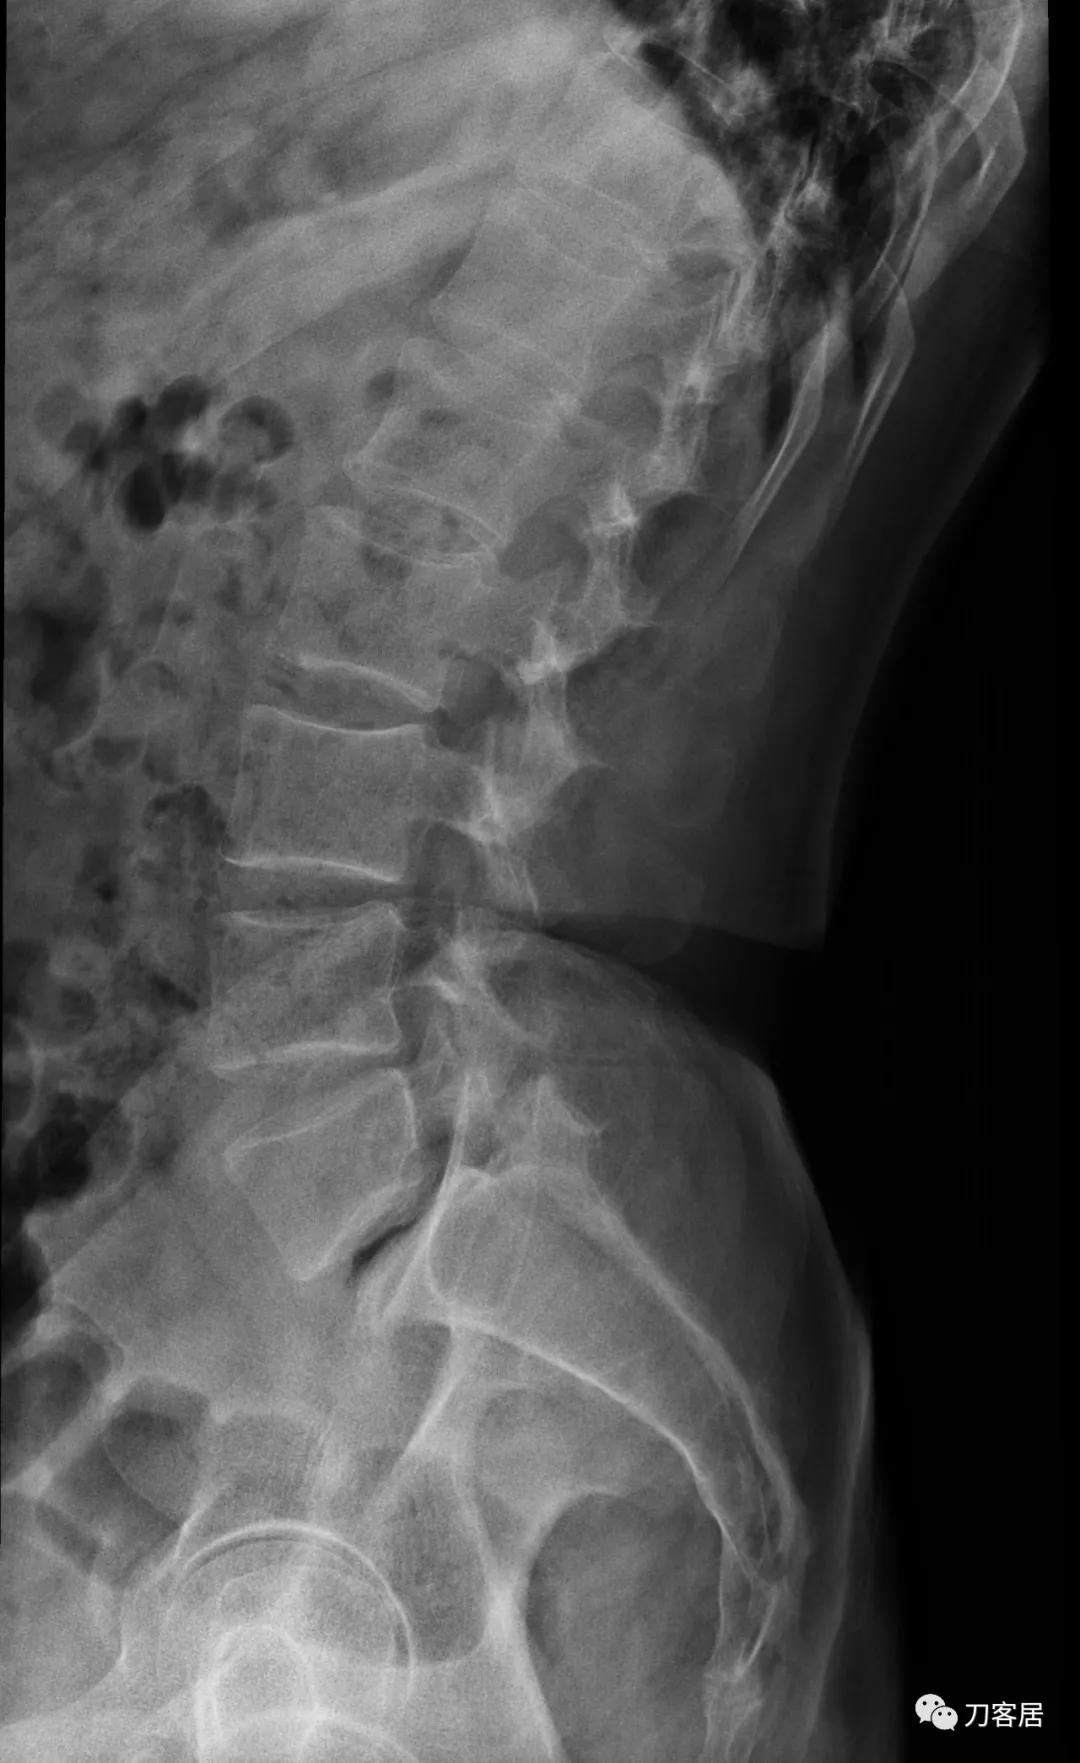

自带影像学检查提示腰5椎体前滑脱,腰5峡部裂,椎管狭窄不严重。

诊断:腰5峡部裂,腰5椎体前滑脱1度,骨质疏松症。

图5. 20210616术前腰椎过伸位X线片